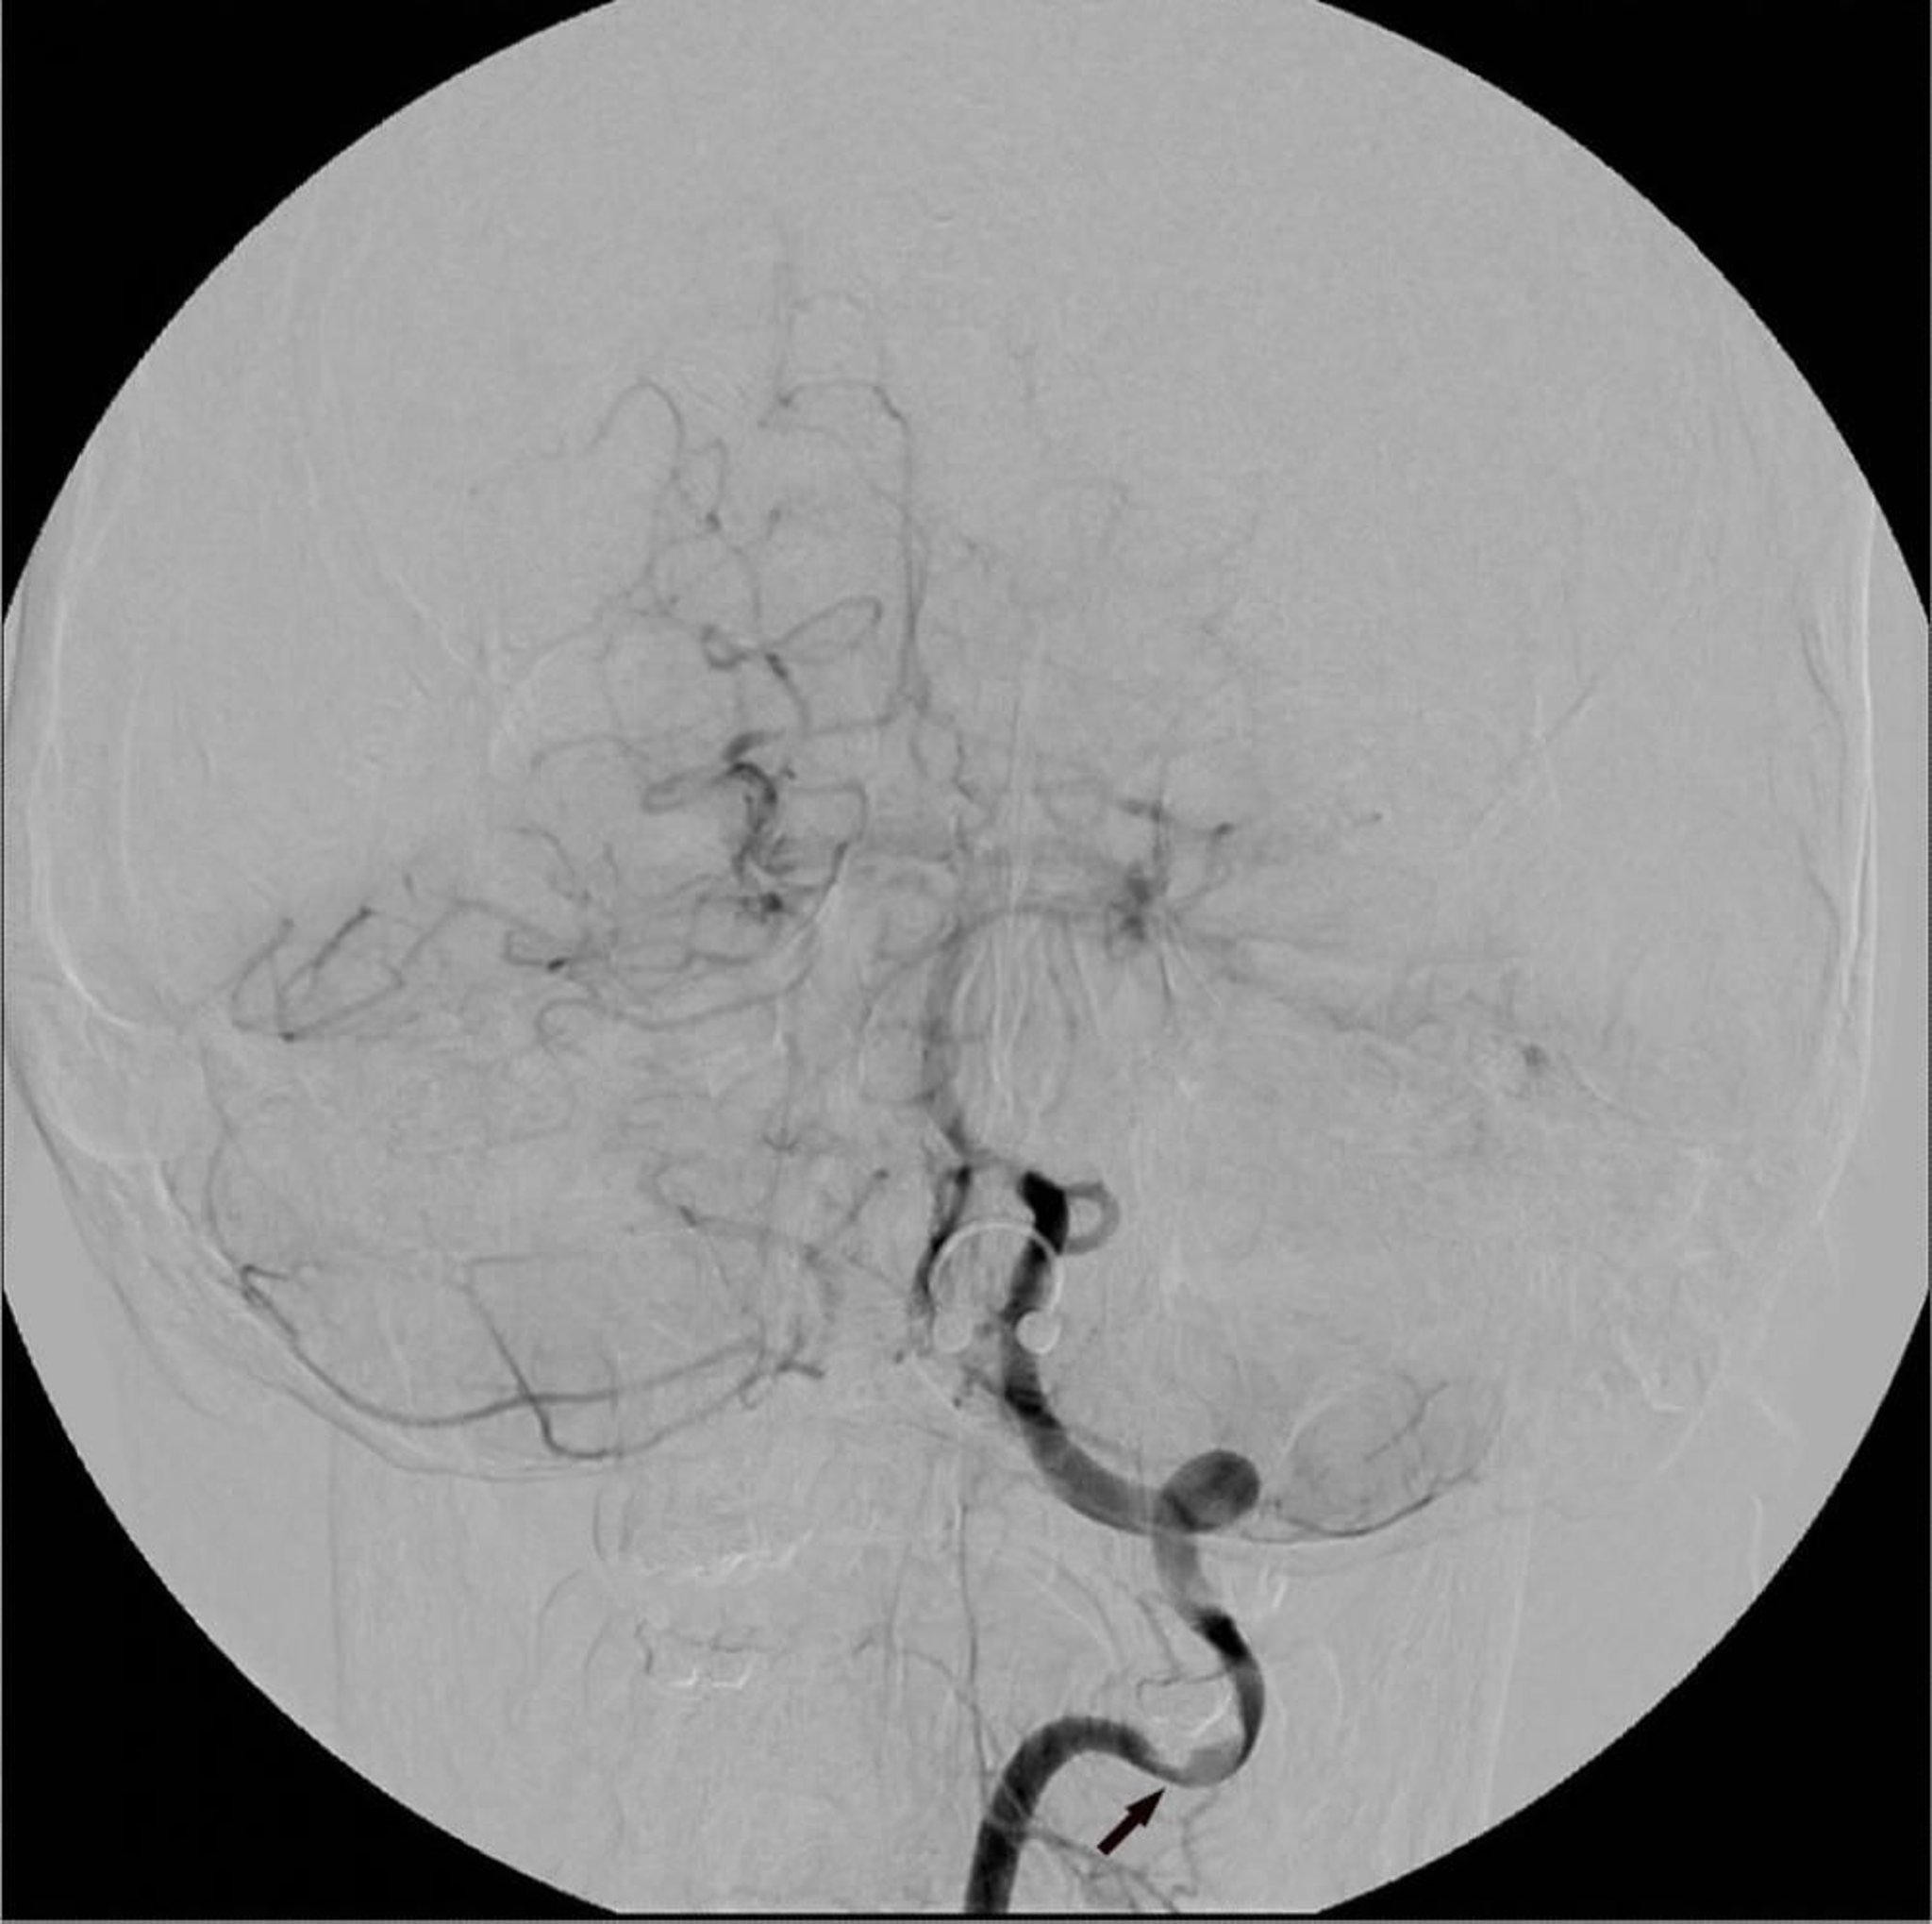

Цифровая субтракционная ангиография

Изображения кровеносного сосуда делаются до и после введения контрастного вещества; затем компьютер вычитает изображение, полученное до введения, из изображения, полученного после введения контрастного вещества. Изображения посторонних структур, таким образом, устраняются, отделяя непрозрачные благодаря контрастному веществу изображения просветов сосудов.

Image courtesy of Hakan Ilaslan, MD.